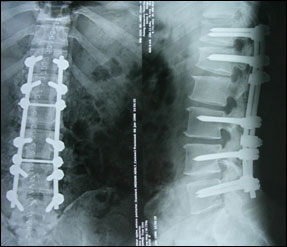

术后腰椎平片:

术后症状缓解明显,可快步行走,半年后自己行走照片: